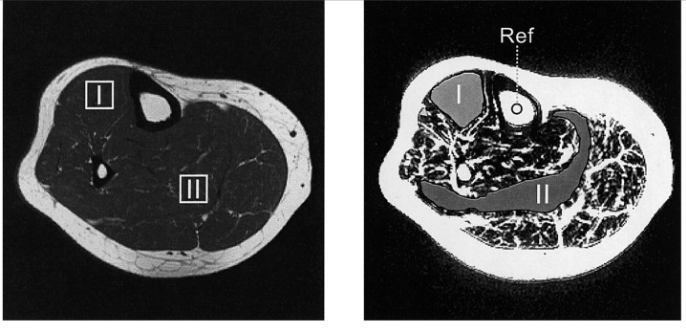

直接看图。这是人小腿的横截面图,画面里白色的纹路都是小腿中的脂质。

▲人小腿的比目鱼肌和胫骨前肌的典型区域的MRI扫描结果图,其中白色为脂质

最外圈那一层厚厚的像围墙一样的是就皮下脂肪。你可以试着做绷脚尖的动作,然后用手指去捏一捏你小腿肚最粗的地方:这时能被你捏起来的软软一层,就是它了。又或者,可以去看看超市里的五花肉:肉皮跟瘦肉之间,就是皮下脂肪所在的位置了。

而小腿中的肌间脂肪分布在肌肉组织内部和周围,你可以形象地把它们理解为“牛排上的雪花”。

图中还可以看到,对于小腿来说,肌间脂肪通常明显少于皮下脂肪——这其实对于“瘦小腿”来说并不是个好消息,因为即使你努力锻炼,最先分解自己给你供能的也是肌间脂肪,而不是那厚厚一层皮下脂肪[3]。

比起肌间脂肪,它不仅更难分解,还很影响肢体外观,这可能是造成你小腿难瘦下来的原因之一。